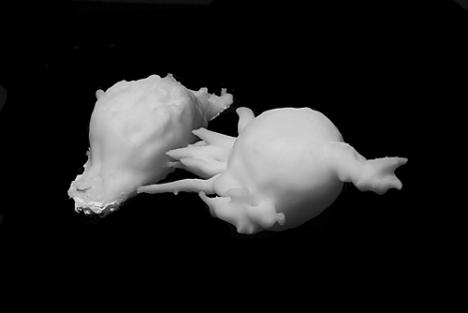

Passée par les écoles Estienne et Duperré, Zoé Tracq, 25 ans, est admise à l’ENS en département design, obtient son DSAA à l’École Boulle, puis l’agrégation en arts appliqués, avant le master 2 de recherche en design. La jeune designer s’oriente vers les sciences du vivant en accomplissant son stage au sein du département de virologie de l’Institut Pasteur. « Nos inventions doivent servir à la vie des gens ! Quand je suis arrivée à Pasteur, personne ne savait pourquoi j’étais là… et moi non plus. L’ENS propose des stages dans des laboratoires sans sujet prédéfini. Chaque étudiant doit faire émerger son thème de recherche en fonction du contexte. » C’est ainsi que Zoé Tracq décide de questionner les modes de représentation des cellules et explore la biologie « comme un atelier où se dessinent et se fabriquent des objets invisibles ». Travaillant sur les cellules infectées par le VIH, la jeune designer a l’idée de les imprimer en 3D, ce qui révélera leurs bras multiples, leur savant équilibre, insoupçonnables sous le microscope qui ne peut restituer l’image de l’objet dans son volume global. L’expérience a enrichi la science et également trouvé un prolongement avec le travail de l’artiste Barthélémy Toguo présenté, en 2016, au Centre Pompidou. Aujourd’hui, dans le cadre de la start-up French Bureau qui accompagne les groupes du CAC 40 dans leurs projets d’innovation, Zoé Tracq réfléchit à l’utilisation de ferments lactiques dans la production des yaourts. Loin du design ? « Je veux continuer à développer une vision globale de la société, à pousser les interactions. Le designer n’est pas seulement là pour dessiner une chaise ! »

Abonnez-vous dès 1 €Impression 3D de deux lymphocytes infectés par le VIH, modélisation sur Imaris et impression par dépôt de fil sur une Zortrax M200, imprimé à l'ENS Cachan

Données issues du Laboratoire Virus et Immunité d'Olivier Schwartz, Photographie François Gardy, sans titre, 2016 © Institut Pasteur